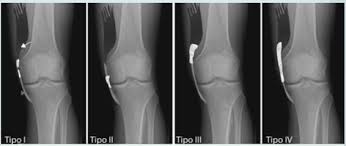

Orif Lag Screw For Lateral Medial Femoral Epicondyle Fracture

Orif Lag Screw For Lateral Medial Femoral Epicondyle Fracture from resources.aofoundation.org